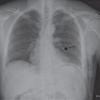

After 3 months of neglection, he sought medical advice. On physical examination, the mass was fluctuant and positive with transillumination, with no systemic signs recorded, blood tests were within normal limits with the absence of infection markers (Fig. 1). Echography was done and showed a 22 × 4.8 cm homogenous hypoechoic mass with some echogenicity seen within swelling of subcutaneous fat. MRI of the right proximal thigh showed longitudinal fluid collection deep to the subcutaneous tissue and superficial to the deep fascia with the previously mentioned size (Fig. 2). A diagnosis of MLL was established and the patient was scheduled for operative treatment with incision, drainage, and debridement. 1.5 L of serosanguinous fluid was drained and necrotic fat was removed from the cavity. This was followed by talc application to increase the chance for recovery. The skin was in good condition so a decision was made to do primary closure with a vacuum drain inserted in the subcutaneous space in addition to compressive dressing. Two weeks later, the drain was removed and the wound healed quite well uneventfully.